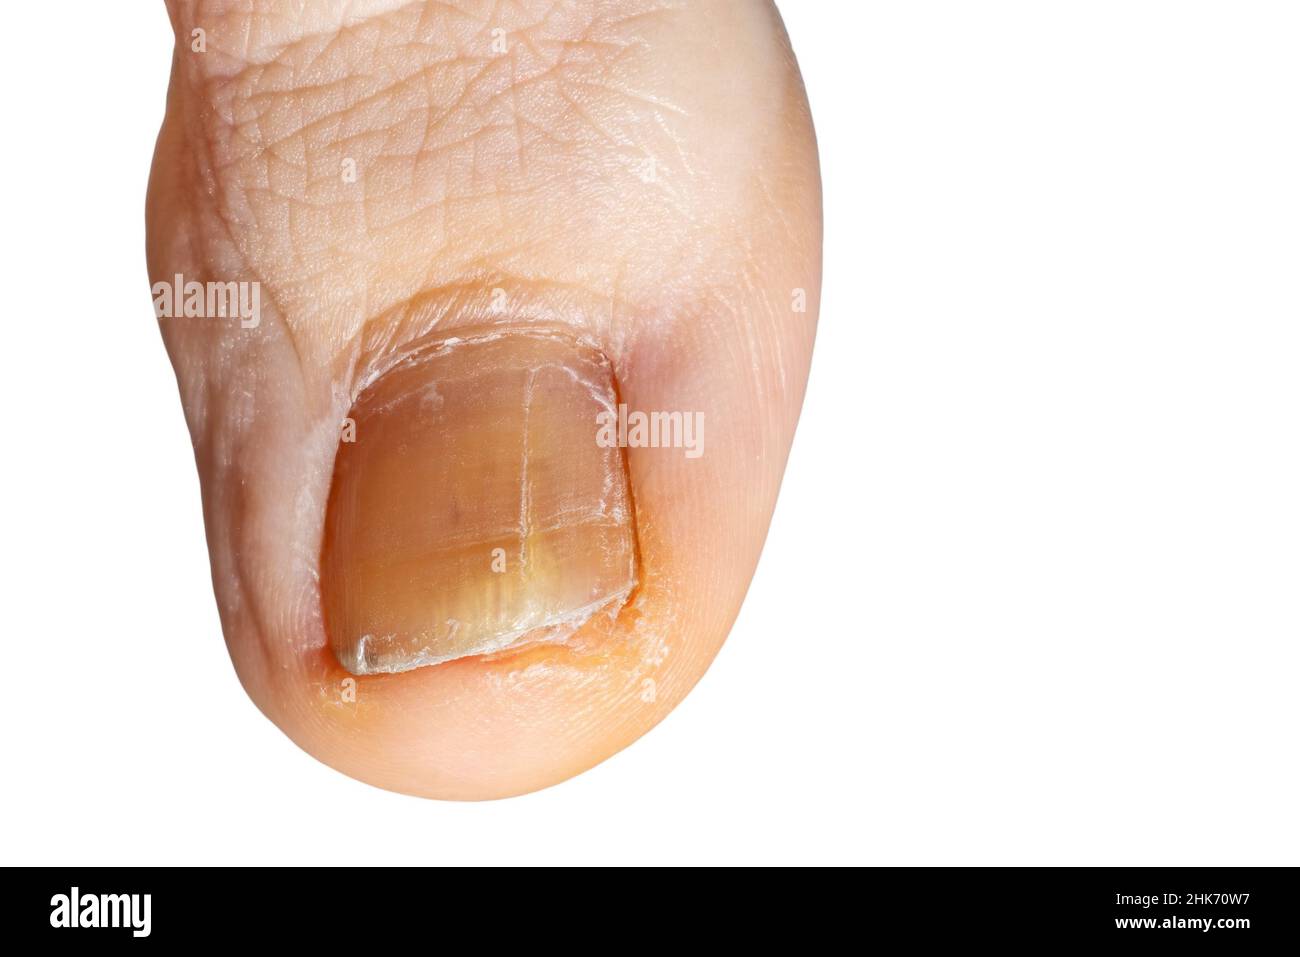

RF2HK70W7–Detail eines Fußnagels mit Pilz. Nahaufnahme der großen Zehe des Fußes mit Pilz auf Nagel isoliert auf weißem Hintergrund

RF2HK70RH–Detail eines Fußnagels mit Pilz. Nahaufnahme der großen Zehe des Fußes mit Pilz auf Nagel isoliert auf weißem Hintergrund